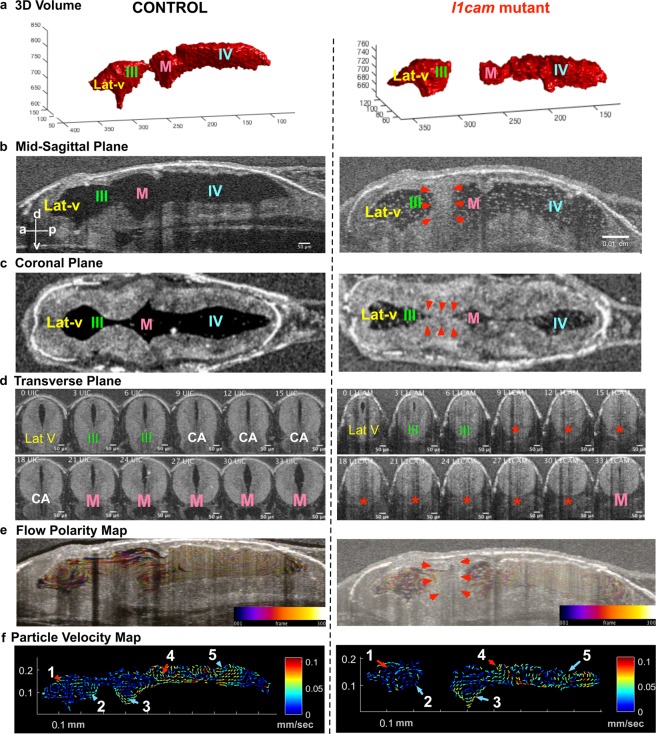

Figure 4. F0 CRISPR mutation in L1CAM causes cerebral aqueduct stenosis. The left column shows control and right column shows l1cam F0 CRISPR mutant images for all panels. (a) 3D rendering of the tadpole ventricular system shows aqueductal stenosis and a smaller ventricular system in l1cam F0 CRISPR mutant. (b) Mid sagittal view and (c) Coronal view of control and l1cam F0 CRISPR mutant, the later showing stenosis of the cerebral aqueduct (red arrowheads). (d) Transverse view of the control and l1cam F0 CRISPR mutant, starting at the end of the lateral ventricle through the cerebral aqueduct and ending in the midbrain ventricle. Control embryo shows normal opening of the duct whereas the mutant shows complete blockage (red star). (e) Relatively normal ciliary flow fields in the control and mutant animals. (f) 2D Particle Velocity Map shows intact FFs 1-5. (Lat-V: lateral ventricle, III: 3rd ventricle, M: Midbrain ventricle, IV: 4th ventricle). |